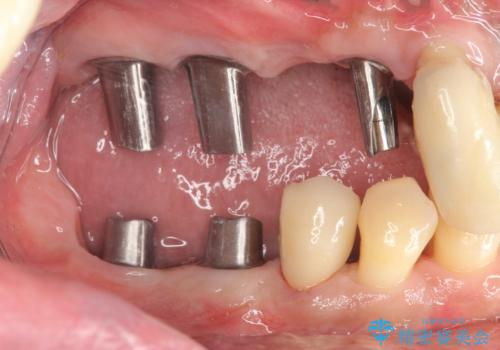

インプラント・ブリッジ補綴を含む、歯周病全顎治療

全体的な歯周病検査を行い、多数の残すことのできない抜歯の必要な歯を認めたため、残せる歯に対しての徹底的な歯周病治療、失った歯に対しブリッジ・インプラント治療を全顎的に行っていくこととしました。